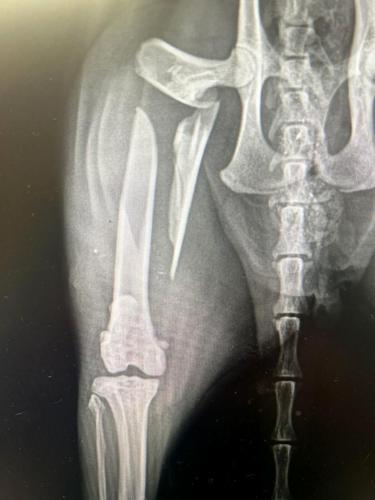

Submitted / TPI An X-ray of the broken leg of Pablo.